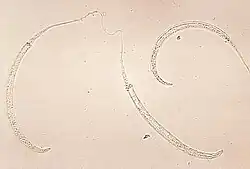

Photomicrograph of larvae | |